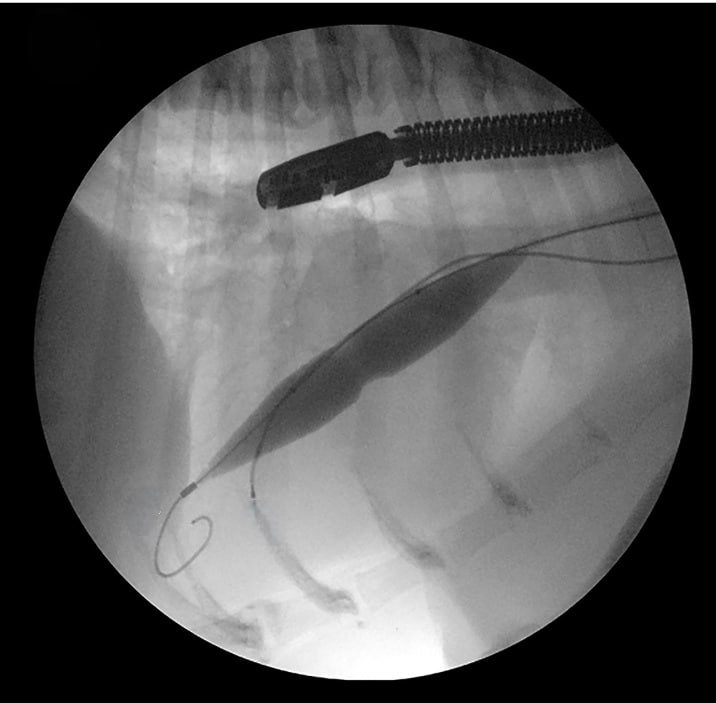

Balloon valvuloplasty is a minimally invasive procedure that uses a catheter-guided balloon to widen the narrowed area and improve blood flow. In more complex cases, a stent may be placed for lasting support. For dogs with pulmonic stenosis, this procedure can significantly reduce symptoms, ease cardiac stress, and improve long-term quality of life.

Pulmonic Balloon /Stent Valvuloplasty

Pulmonic stenosis is a common congenital heart defect that causes narrowing at or near the pulmonary valve, making it harder for the heart to pump blood to the lungs. Over time, this extra strain can lead to fatigue, fainting, or even heart failure.